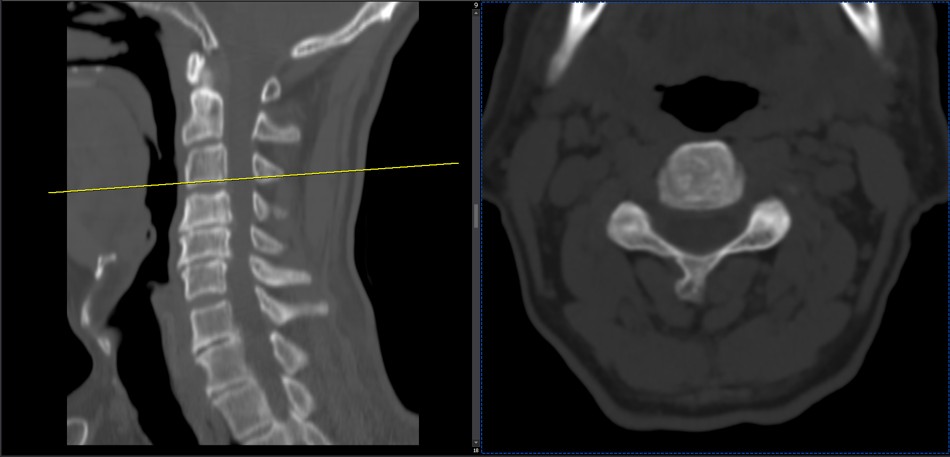

41 years old man presented to my clinic in October 2023 with acute and sever R neck pain with radicular pain to his R upper extremity along C6 dematom since 2 weeks ago. Examination didn’t show any upper motor signs. Was suggested urgent surgery

I ordered EMG/ NCV : showed mild R C6, C7 irritation without any active axonal loss

In his MRI was reported R. para R. IVF Massive extrusion. I decided to control his pain and manage this patient with reevaluation of patient every other session. For 5 sessions i just used acupuncture and laser and IFC and mild adjustments to his R. T3-T7 and mild arthosteem to above and below involved segment. Cervical adjustment considered contraindicated for this patient. From session 6th- 8th i started to use mild/gentle cervical decompression. He used soft cervical collar all the time. His pain decreased by 80 percent

I gave him cervical traction pump to be used 3-5 times per day at home for the next 3 months and i released the patient. He was evaluated every week once for one month and after that every 2 weeks. After 3 month I repeated MRI. Size of the herniated disc was reduced greater than 50 percent. Asked him to do another mri in 6 months

MRIs before and after proper management of this patient: